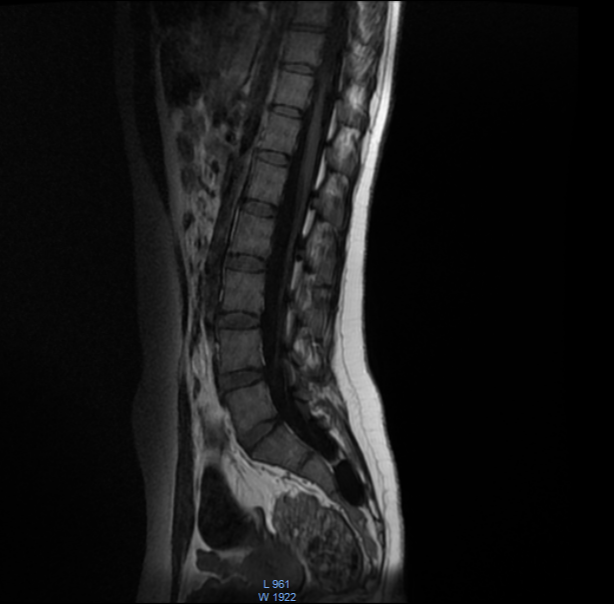

تبين بصورة الرنين وجود كيس في المنطقة العجزية حجمه ٣ سم وأكثر بقليل

هذه الالام مفسرة من الكيسة وضغطها على الاعصاب

وهي لا تستجيب على الادوية ويفضل استصالها جراحيا